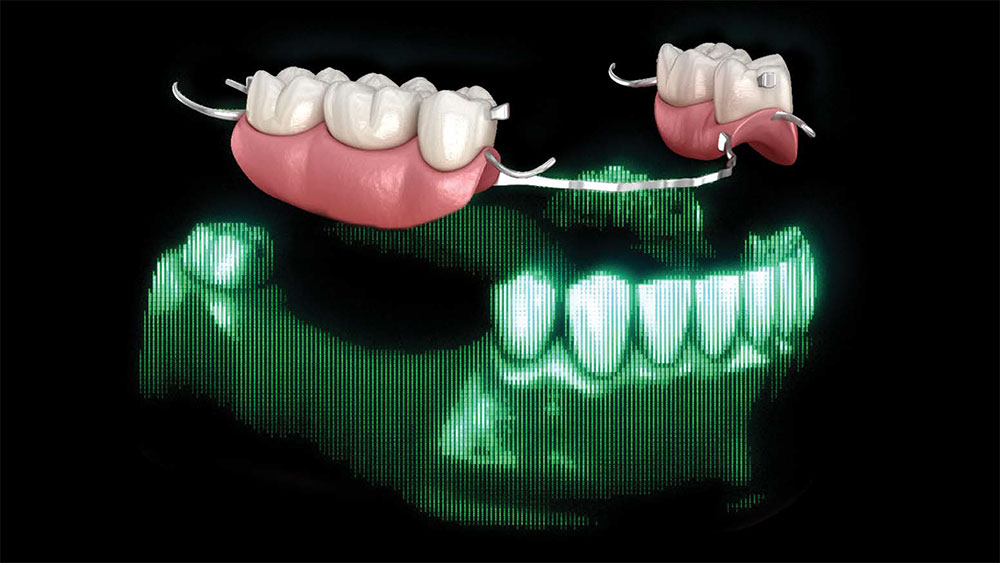

When a patient presents with an existing removable partial denture that still fits well, but one of the abutment teeth requires a new crown, clinicians face a common challenge: how to fabricate a new crown without forcing the patient to go without their partial. Patients grow attached to their partials — both functionally and emotionally. Asking them to go without their appliance, even for a few days, can be uncomfortable and inconvenient for them.

Traditionally, this process involved multiple appointments, analog duplication, and tedious adjustments. Today, by digitally duplicating the partial’s intaglio surface, clinicians can design a crown that precisely conforms to the appliance’s contours. The result is a restoration that fits seamlessly beneath the existing partial, eliminating the need for patients to go without it during fabrication.

For any new crown to fit properly under an existing appliance, the crown must conform to its clasps, rests and axial contours. It’s important to pay close attention to the fit of the existing appliance.

For existing partials, examine the occluding tooth contact, the position of the tongue, how the retentive and reciprocal arms are placed, and how it rests on the occlusal surface of the crown. Be sure to also examine the patient’s oral environment when the partial is removed, noting the spacing and the gingival region around the crown.